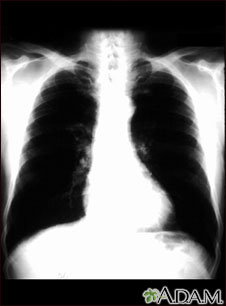

This is a chest x-ray of a person with bronchial cancer. This is a front view. The lungs are the two dark areas. The heart and other structures are white areas visible in the middle of the chest. The light areas that appear as subtle branches extending from the center into the lungs are cancerous.